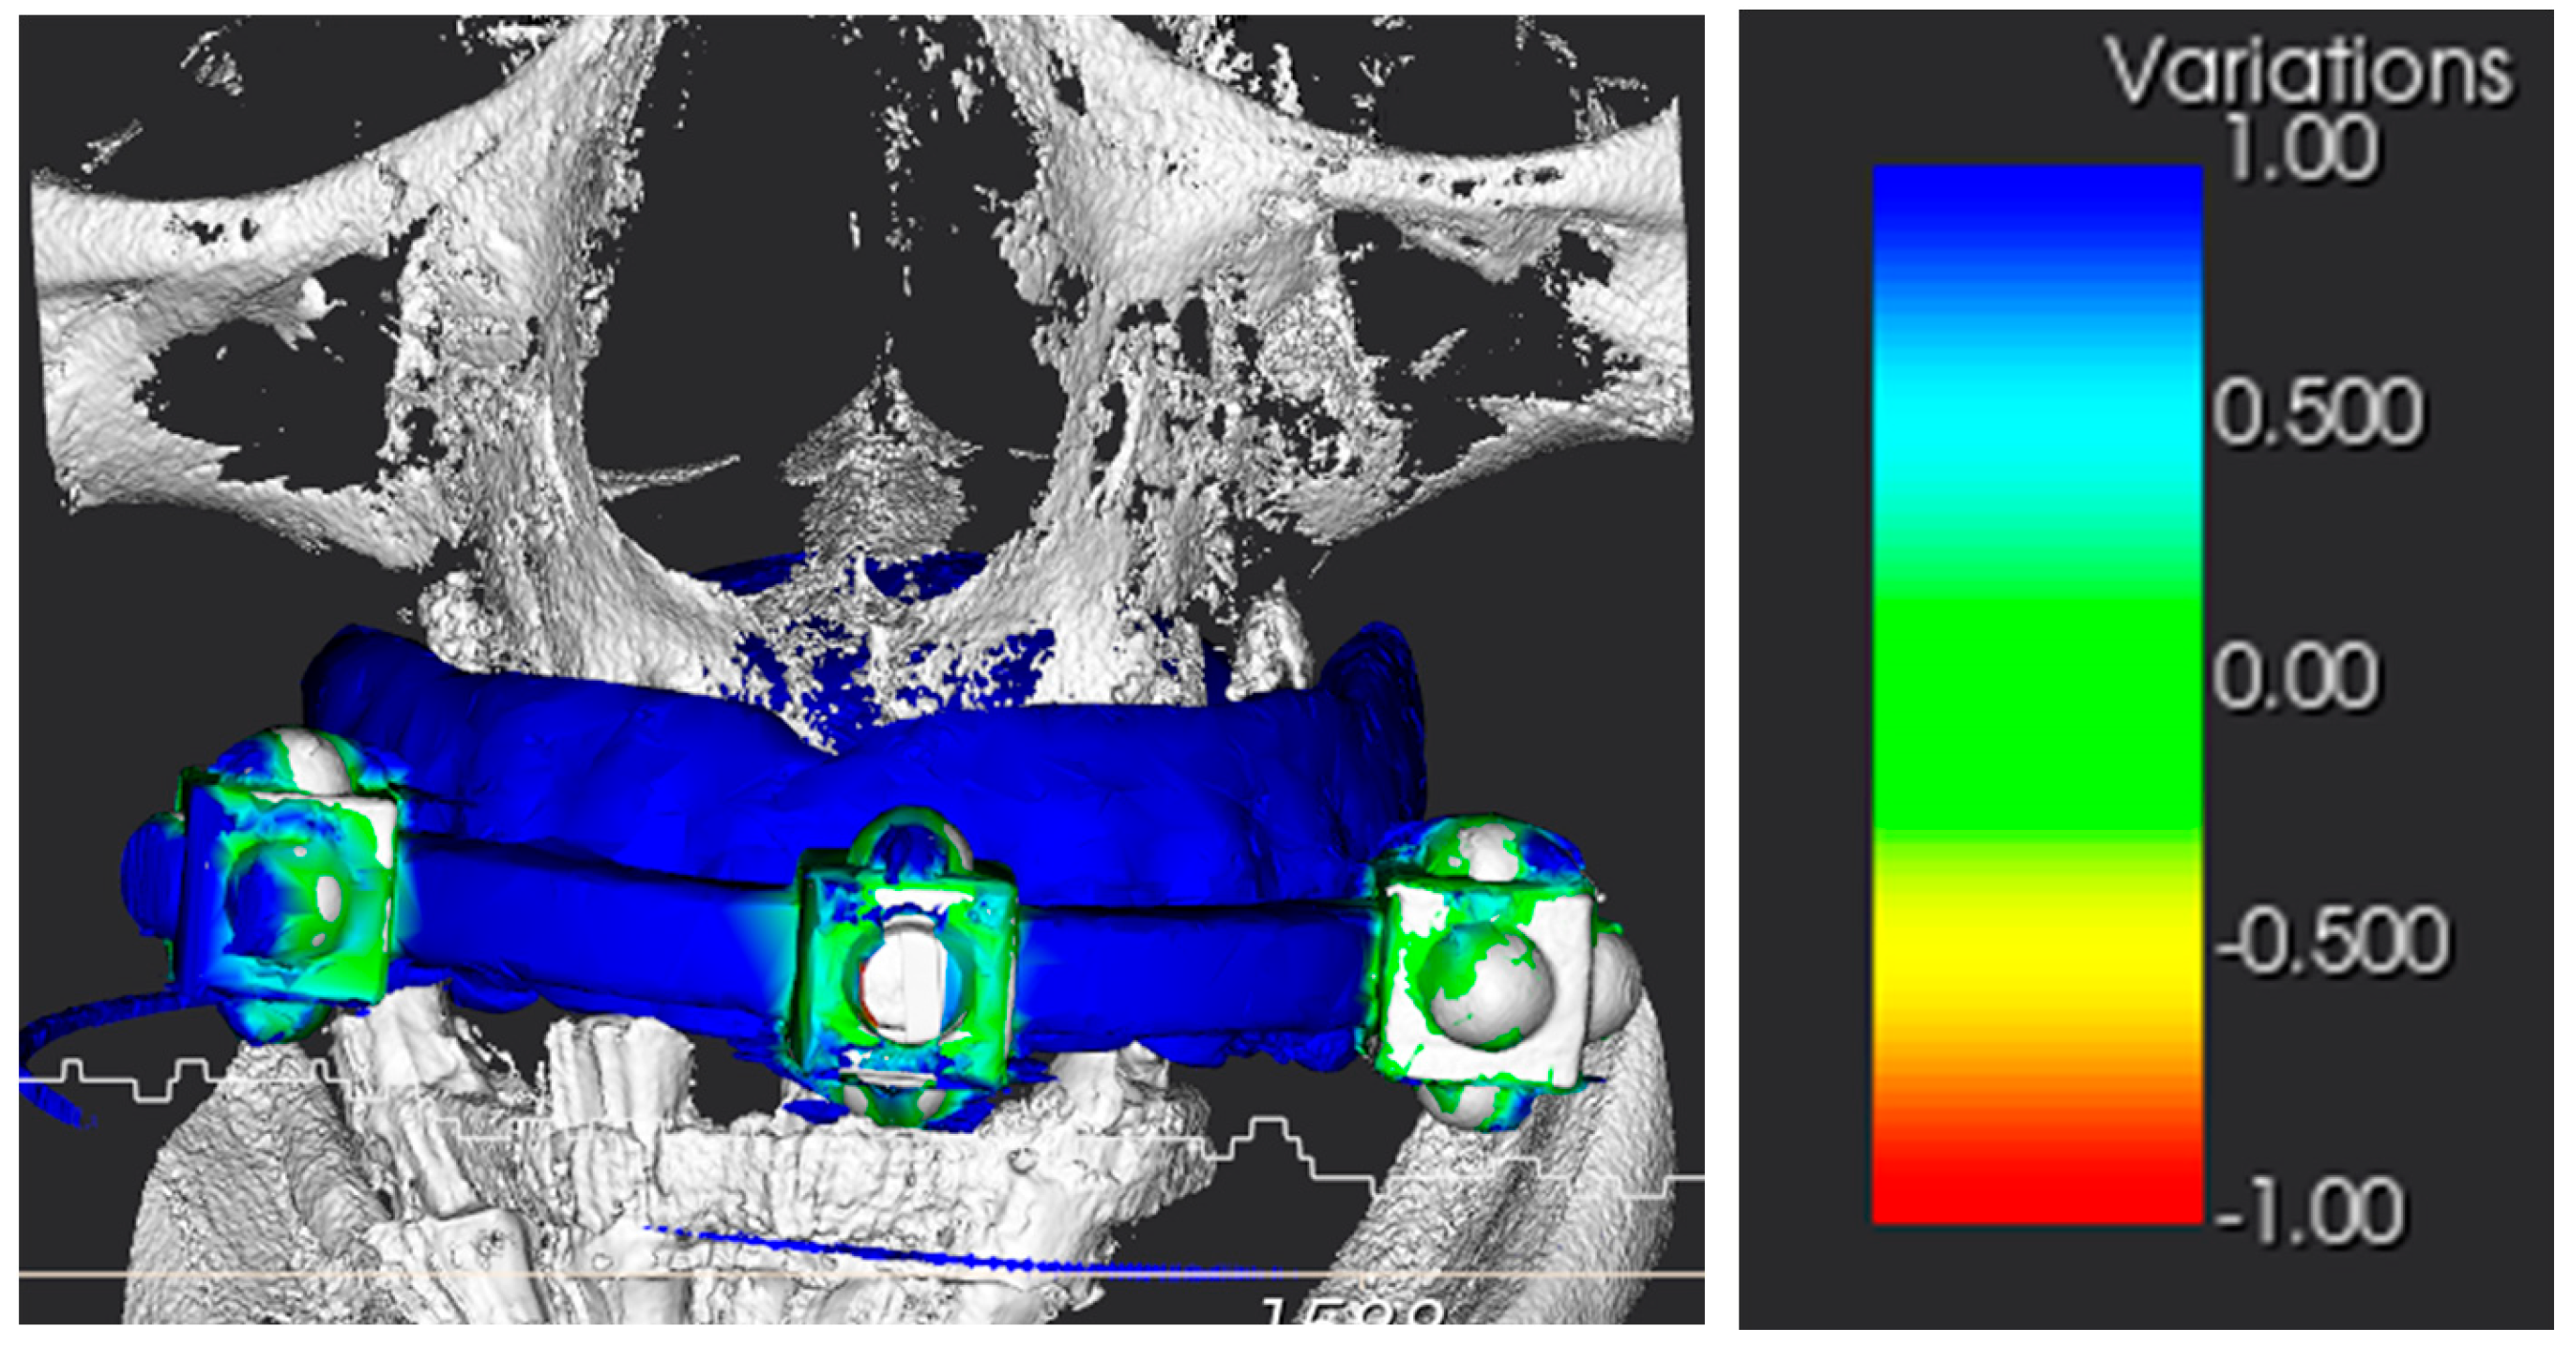

3.1. Alignment Accuracy

3.2. Surgical Guide Accuracy